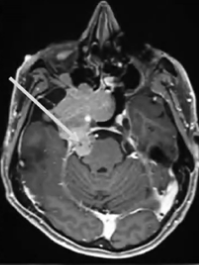

2012年,53岁的Leo突然发现自己嗅觉减退、视力下降时,就医检查发现右侧梅克尔腔脑膜瘤,随即进行了手术。谁能想到7年过后,脑膜瘤再次卷土重来,出现严重的V1(嗅神经)、V2(视神经)和V3(动眼神经)感觉减退和疼痛,症状比第一次手术前还要严重。磁共振成像(MRI)显示肿瘤大面积复发,延伸至海绵窦(CS)、后颅窝(PF)、蝶窦(SS)、翼腭窝(PPF)和颞下窝(ITF)。这个张牙舞爪的肿瘤,属实不太容易切除。

患者术前影像。(A)术前轴位T1加权钆增强磁共振成像(MRI),显示脑膜瘤延伸至后颅窝、海绵窦、眼眶和蝶窦。(B)肿瘤延伸至中颅窝、翼腭窝和颞下窝。(C)术前轴位计算机断层扫描(CT)显示蝶骨大翼侵蚀和蝶窦受累。

最终,手术顺利完成,根据术前术后影像对比,患者肿瘤得到完全切除。